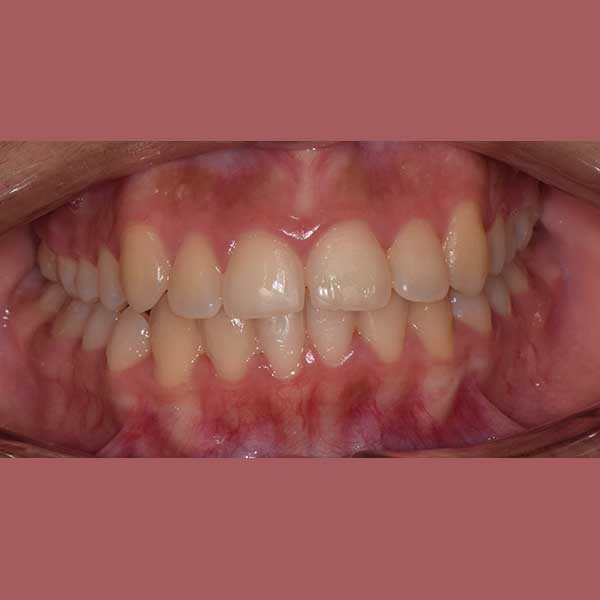

AFTER

النتيجة النهائية:

كما تظهر الصور، نجحنا في رصف الأسنان بشكل ممتاز وتحقيق إطباق مثالي. عاد الناب المرتفع إلى مكانه الطبيعي ضمن ابتسامة متناسقة وجميلة، مما أعاد لمراجعتنا الثقة والسعادة بابتسامتها.